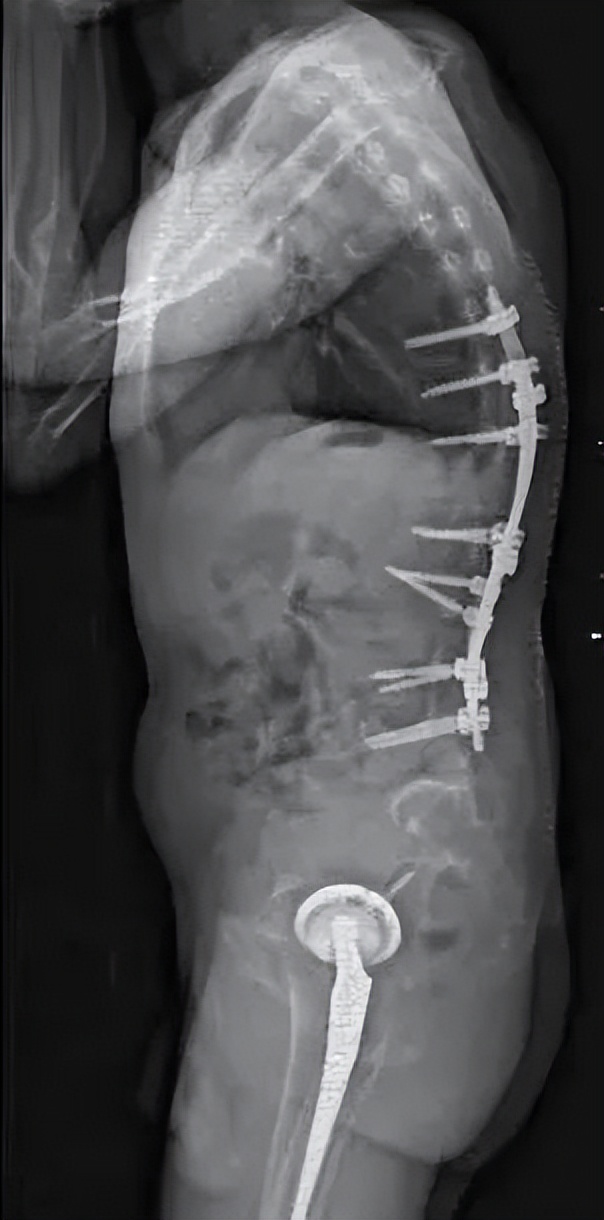

患者又回到了最信任的北京积水潭医院,找到了髋关节手术的主刀医生周一新主任,由周主任介绍到脊柱外科。脊柱外科经过全科查房讨论,制定周密的术前规划,综合考虑患者的直立、平视、端坐、平躺等功能,设计截骨位置并计算截骨角度,最终确定了L3、T12双节段经椎弓根截骨的矫形方案。在麻醉科、手术室、肌电图室、ICU、输血科、脊柱外科等多方面合作下,手术顺利完成。患者术后即可完全平躺,下地后可完全直立并且平视。手术效果非常满意,患者重新挺起胸膛,开启新的人生。